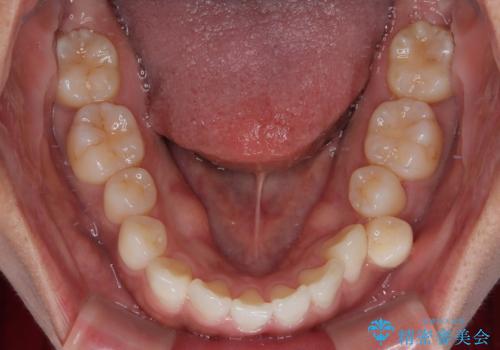

初診時、上下顎ともに歯列の不正が認められ、特に左下の小臼歯が大きく歯列から外れている状態でした。その影響により、下顎の正中が左側へシフトしており、見た目だけでなく噛み合わせにも影響が出ていました。

左下の小臼歯をきれいに歯列内へ並べるためには、まず十分なスペースの確保が必要でした。

そこで本症例では、上顎右側にアンカースクリュー(矯正用インプラント)を埋入し、そこからゴムかけ(顎間ゴム)を行うことで、下顎の正中を右方向へコントロール。

これにより、左下小臼歯がく並ぶためのスペースを確保することができました。

「歯並びと正中が整って、自信をもって笑えるようになった」

と大変ご満足のお言葉をいただきました。